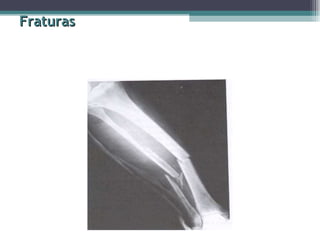

Fraturas Quanto ao traço de fratura   Incompleta: ocorre a lesão óssea, mas não rompe a continuidade óssea; tipo de ocorrência comum em crianças.  Completa: os fragmentos ósseos perdem a continuidade, ficando desviados ou não.

Fraturas Quanto aotraço de fratura Incompleta: ocorre a lesão óssea, mas não rompe a continuidade óssea; tipo de ocorrência comum em crianças. Completa: os fragmentos ósseos perdem a continuidade, ficando desviados ou não.